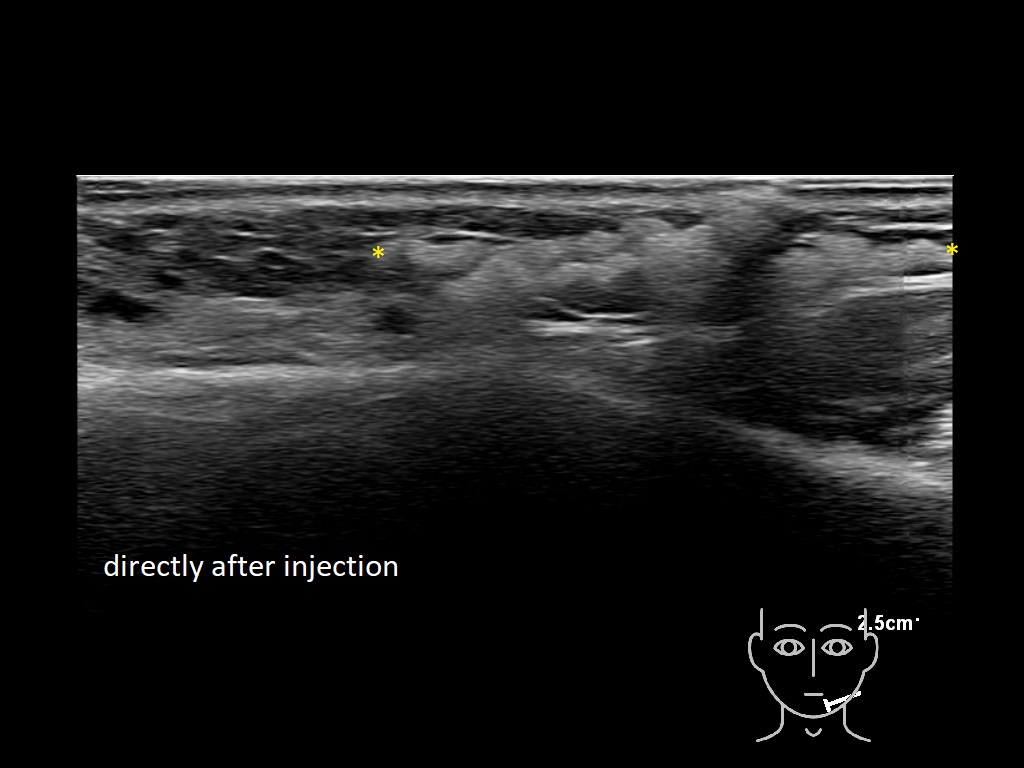

Draw in the image on the right where the fillers are located. To check if your answer is correct, please click on the secondary image.

Draw in the second image below where the fillers are located. To check if your answer is correct, swipe the first image to the right.